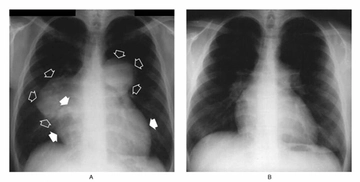

Akciğer tansiyonu, pulmoner hipertansiyon olarak da bilinen bu durum, akciğerlerdeki kan damarlarının basıncının normalden daha yüksek olması anlamına gelir. Bu rahatsızlık, kalp ve akciğer fonksiyonlarını etkileyebilir ve ciddi sağlık sorunlarına yol açabilir. Bu makalede, akciğer tansiyonunun insan sağlığı üzerindeki etkileri, belirtileri, nedenleri ve tedavi yöntemleri detaylı bir şekilde ele alınacaktır. Akciğer Tansiyonu Nedir?Akciğer tansiyonu, akciğerlerdeki kan damarlarındaki basıncın yükselmesi sonucu ortaya çıkar. Normalde, akciğerlerdeki kan damarlarının basıncı 8-20 mmHg arasında olmalıdır. Ancak bu değerlerin üzerinde bir ölçüm, pulmoner hipertansiyon olarak kabul edilir. Akciğer tansiyonu genellikle, kalp sağlığı üzerinde de olumsuz etkiler yaratır. Akciğer Tansiyonunun BelirtileriAkciğer tansiyonu, birçok belirti ile kendini gösterebilir. Bu belirtiler, hastalığın şiddetine göre değişiklik gösterebilir. Yaygın belirtiler şunlardır:

Akciğer tansiyonu, pulmoner hipertansiyon olarak bilinir ve akciğerlerdeki kan damarlarının basıncının yükselmesi durumudur. Bu durum, kalp sağlığını doğrudan etkileyebilir çünkü kalbin sağ ventrikülü, akciğerlerden gelen kanı pompalamak için daha fazla çalışmak zorunda kalır. Uzun vadede bu durum kalp yetmezliğine yol açabilir.